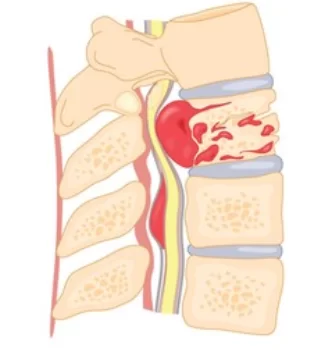

Οι σπονδυλικές μεταστάσεις είναι οι πιο συνηθισμένοι όγκοι της σπονδυλικής στήλης, και αποτελούν περίπου το 90% των όγκων που ανακαλύπτονται στη σπονδυλική στήλη. Συνήθως παρουσιάζονται ως μεταστάσεις εντός των σπονδύλων, αν και σε ένα ποσοστό 20% ο όγκος μπορεί να επεκτείνεται μέσα στο σπονδυλικό σωλήνα και να πιέζει το νωτιαίο μυελό. Η συνηθέστερη εντόπιση είναι η θωρακική μοίρα της σπονδυλικής στήλης, ακολουθούμενη από την οσφυϊκή και την αυχενική.

Ένα χαρακτηριστικό των σπονδυλικών μεταστάσεων είναι ότι δεν επεκτείνονται στον μεσοσπονδύλιο δίσκο και αυτό βοηθά να τις ξεχωρίσουμε από τις φλεγμονές της σπονδυλικής στήλης. Η επέκταση των καρκινικών κυττάρων στη σπονδυλική στήλη μπορεί να γίνει με διαφόρους τρόπους, ο πιο συχνός όμως είναι η αιματογενής διασπορά μέσω των φλεβών του σπονδυλικού σωλήνα.

Ο πόνος είναι το πιο συχνό σύμπτωμα για το οποίο παραπονιούνται οι ασθενείς με μεταστάσεις στη σπονδυλική στήλη. Αν κάποιος ογκολογικός ασθενής παραπονεθεί για πόνο στη μέση ή στη ράχη, ο γιατρός του θα πρέπει οπωσδήποτε να αποκλείσει τις σπονδυλικές μεταστάσεις. Ένα χαρακτηριστικό του πόνου είναι ότι είναι πιο έντονος τη νύχτα και δεν αφήνει τον ασθενή να κοιμηθεί. Αν ο όγκος επεκτείνεται εντός του σπονδυλικού σωλήνα μπορεί να προκαλέσει νευρολογικά προβλήματα όπως αδυναμία και μουδιάσματα στα κάτω άκρα, δυσκολία στη βάδιση ή ακόμα και προβλήματα με την ούρηση και το έντερο.

Αν όμως ο όγκος επεκτείνεται εντός του σπονδυλικού σωλήνα και πιέζει το νωτιαίο μυελό τότε η στρατηγική αντιμετώπισης αλλάζει σημαντικά! Στην περίπτωση αυτή πρέπει να γίνει άμεσα χειρουργική αποσυμπίεση προκειμένω να μην εγκατασταθεί μόνιμη βλάβη. Μελέτες έχουν δείξει ότι η παράλυση λόγω μεταστάσεων στη σπονδυλική στήλη καθηλώνει τους ασθενείς και μειώνει το προσδόκιμο επιβίωσης. Αντίθετα, η χειρουργική αποσυμπίεση βελτιώνει τη νευρολογική εικόνα και κατ’ επέκταση την πρόγνωση.